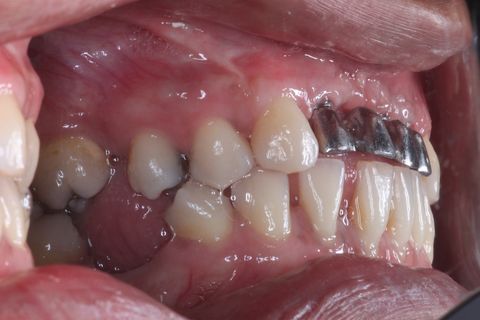

Foto Perfil (uso de espelho). Lado Direito

Foto oclusal superior